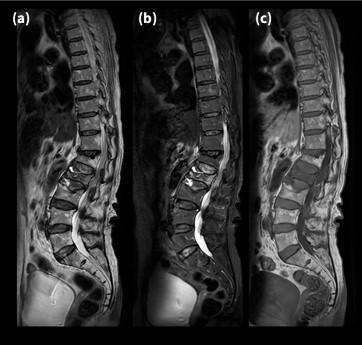

Fig.2にAIR™ Recon DL(以下ARDL )を用いた頭部T2WIを示す。本画像は、受検者が極度の閉所恐怖症を有し、ガントリー内には入れたもののHeadコイル前面を装着することに抵抗を示したため、馬蹄アダプタをHeadコイルに装着して撮像を行った症例である。本法では、頭部前面の感度不良域をPureにて補正し、信号上昇によって生じたノイズをARDLで抑制した。ARDLを用いた画像のみを見ると一見何の違和感を抱かないが、ARDLを用いない画像と比較するとその威力を感じることができる。また、本技術はSNRの向上のみならず尖鋭性の向上効果も高いことが特徴であり1)、その臨床例については後述する。

VoyagerMR30_ube03.jpg

Fig.2 馬蹄アダプタを装着したHead coilで撮像 したT2WIにおけるDL有無の比較

(a) without Pure, without DL (b) with Pure, without DL (c) with Pure, with DL(H) (d) localizer image